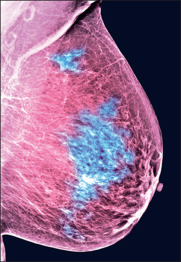

Breast cancer is caused by a mutation in breast cells. As a result of this process, they divide uncontrollably and spread through the breast tissue. These cells form a tumor, which you can detect on palpation of the breast or mammography. Therefore, women should see a doctor every six months to reduce the risk of cancer.

Depending on the location of the tumor, doctors recognize the type of cancer and prescribe treatment. At the same time, the tumor can appear in different parts of the breast, grow in one place, or spread through the lymphatic system throughout the body.